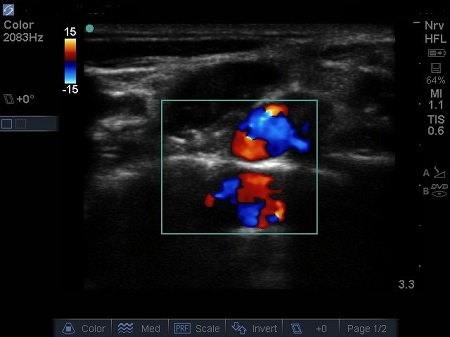

- The first structure to locate is the round pulsating hypoechoic subclavian artery (A), lying on top of the hyperechoic first rib (R). Use Doppler to assess for vessels. See Fig. 2.

Fig. 2. Bidirectional Doppler used here to highlight the subclavian artery.

Hypoechoic vessels may be seen among the brachial plexus nerves (also round hypoechoic structures). Because they have similar appearance, it is important to differentiate them (colour Doppler MUST be used) (16). See Fig. 9.

Fig. 9. Doppler highlighting subclavian artery with dorsal scapular artery passing posteriorly through brachial plexus.